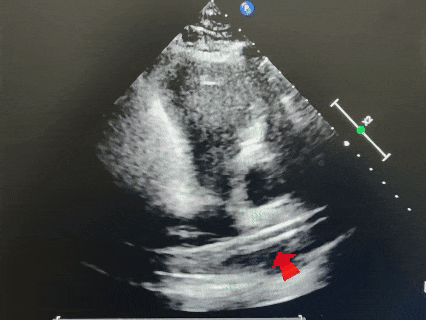

主动脉短轴切面

四腔心切面

超声下可见封堵器稳定夹持在房间隔两侧,呈“Y”字形牢牢抱住主动脉,盘面贴合,形态良好。